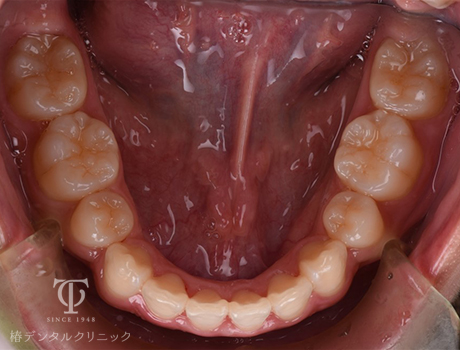

マウスピース装着後

Case01

-

- 症状

- 前歯の歯並びがずれてきた

- 治療期間

- 約5か月

- 治療費用

- 330,000円

以前全顎矯正をしていて後戻りをおこしてしまった患者様です。軽度の叢生のため、マウスピース矯正をおこないました。